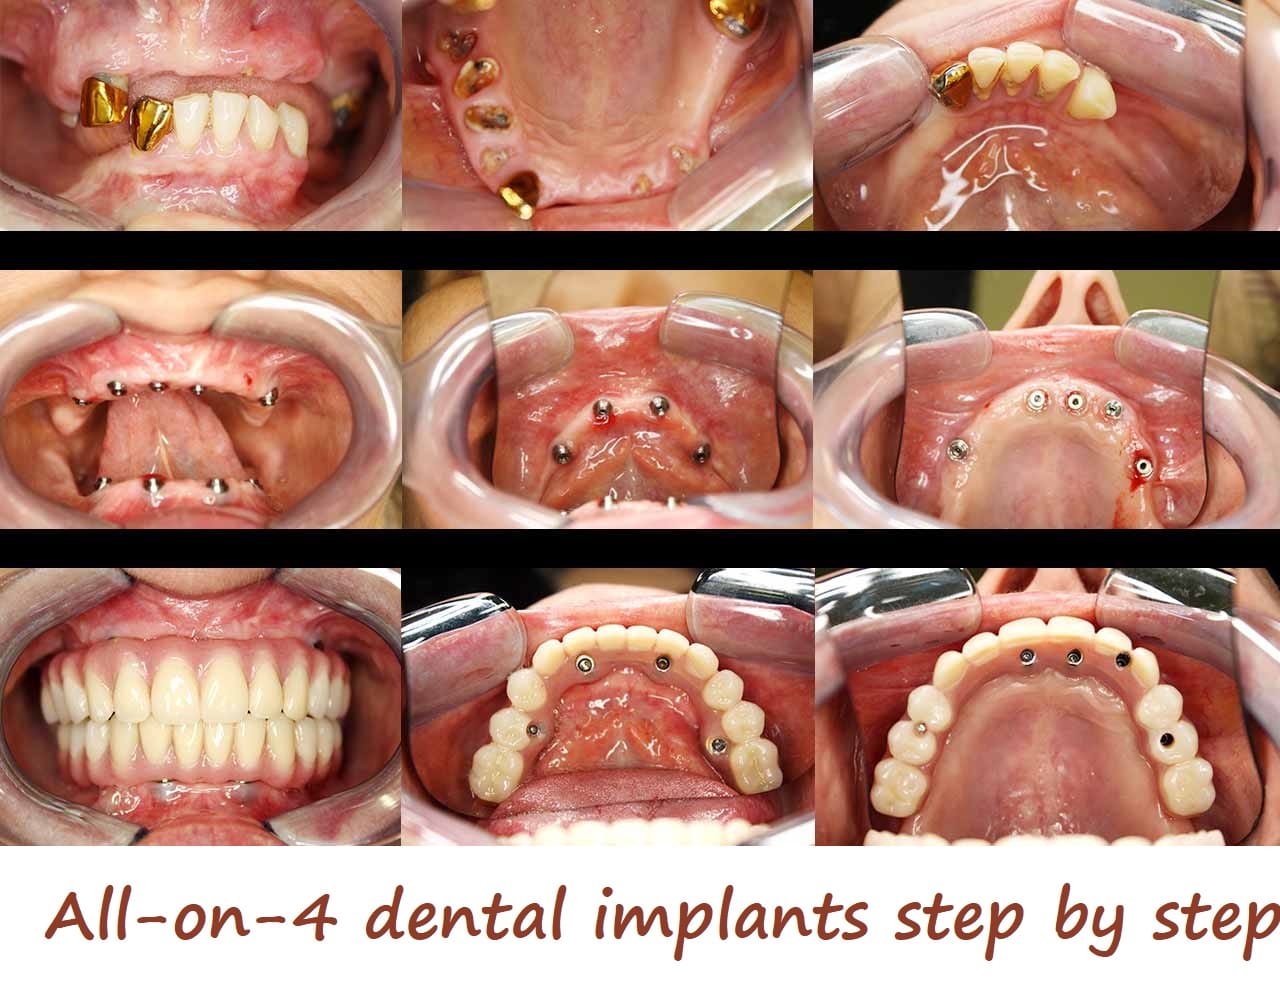

All on X implant systems include All on 4, All on 6 and All on 8 implant systems, which differ in how many screws are used per bridge. They are the best choice for patients who want to have the most affordable and very durable implant system for restoring many teeth at once. Patients who have more dense jaws and desire even better stability can choose All on 6 systems. More information about our All on X implant procedures, including All on 4 dental implants.

All on 4 implant systems have four screws per bridge and are among the most popular options at our clinic. Their cost is the lowest among all All on X systems.